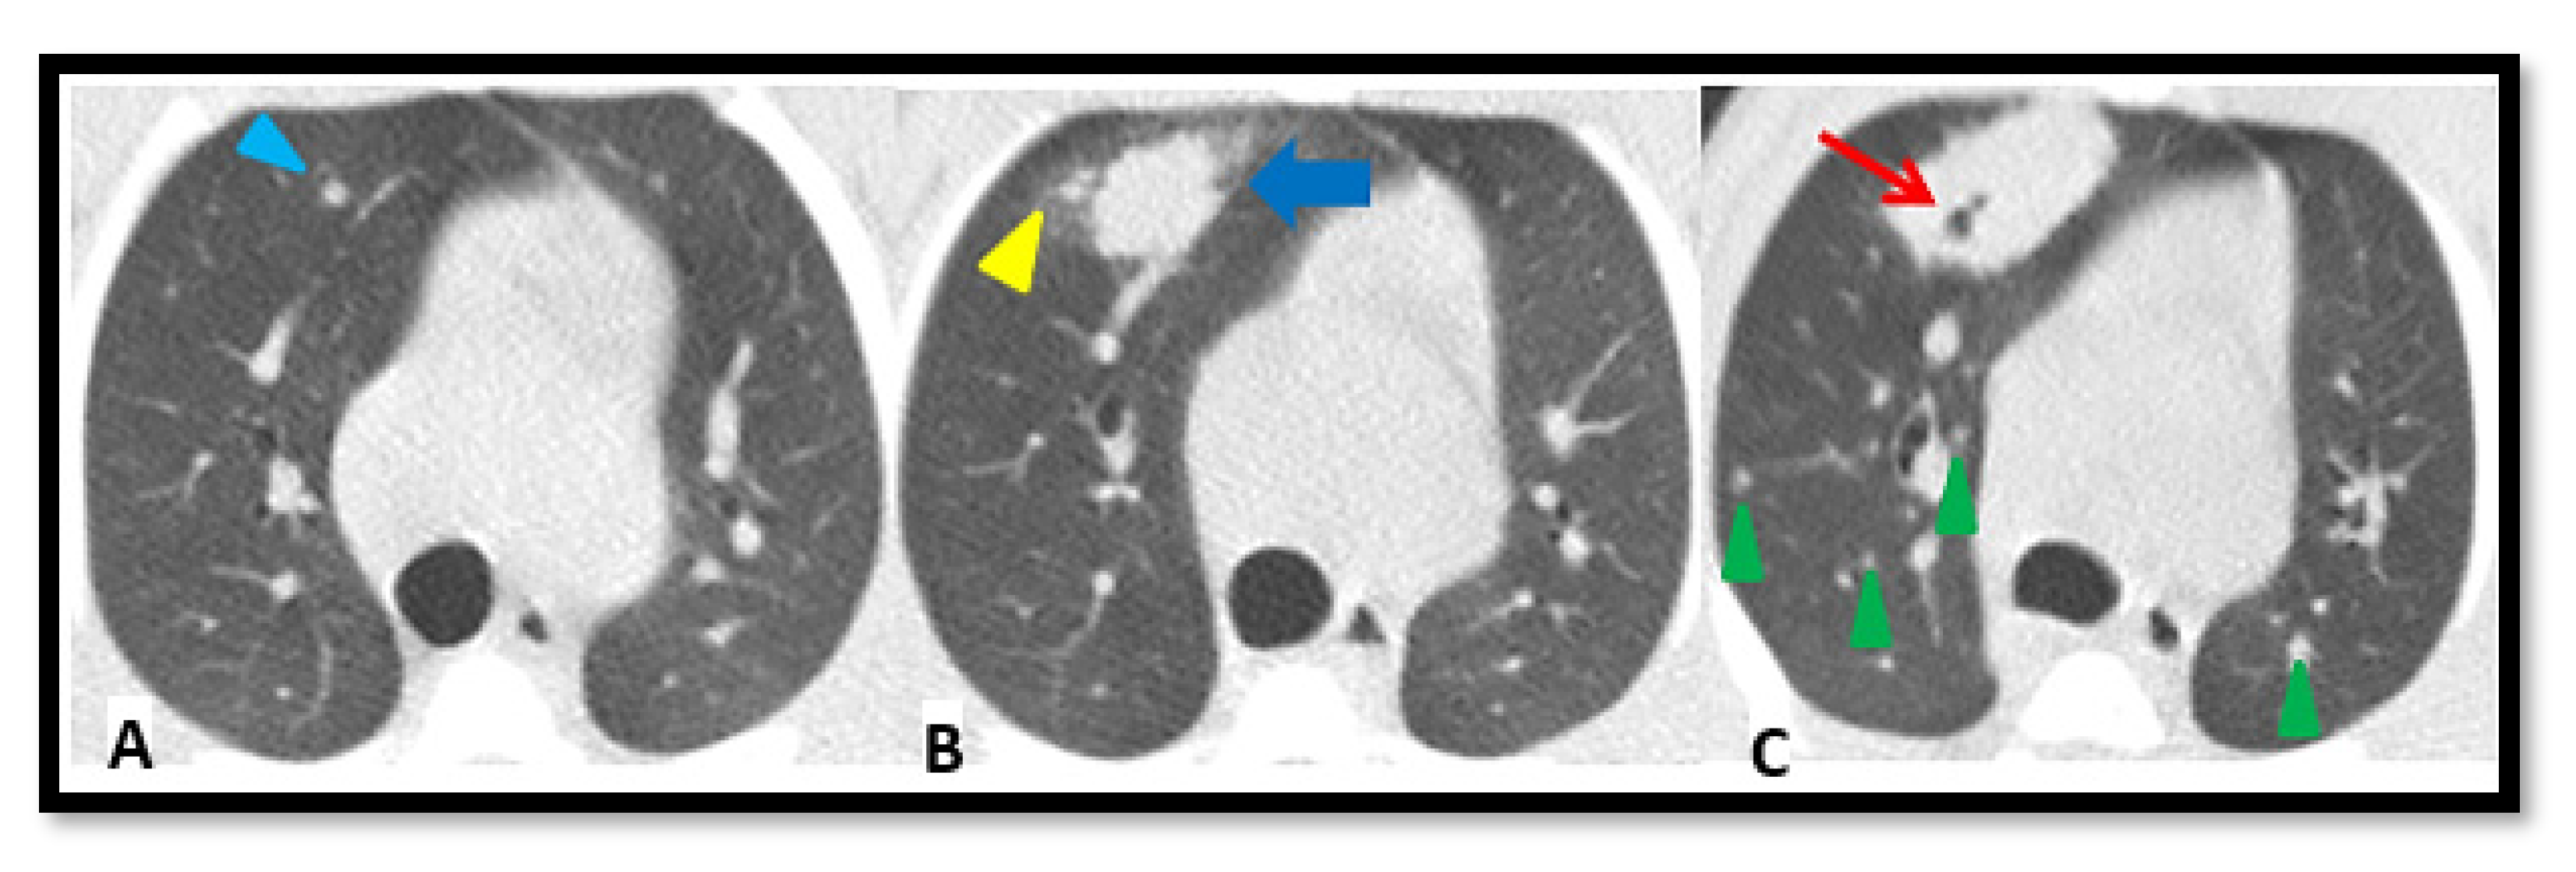

2.4. TB Lung Lesions Analysis from CT Images

- A.

- Micronodule is a small solid lung nodule with smooth margins.

- B.

- Consolidation (also referred to as consolidated lesion) is a pneumonic patch or necrotizing consolidative process that occupies and even destroys alveoli, and it is described in CT images as a soft tissue lesion within lung parenchyma showing irregular margins.

- C.

- D.

- Pleural distance is defined as the distance between the margin of each consolidation to the closest pleura or fissure.